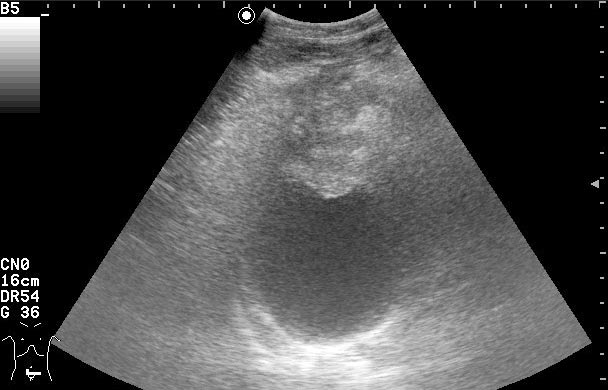

Пациентке была выполнена биопсия образования, назначена антибактериальная и противовоспалительная терапия.

Клиническое выздоровление через 2 недели. Сонограммы мочевого пузыря через 6 недель:

Если бы это было воспаление кисты, то мы бы видели изначально кисту с акустически непрозрачным содержимым. После лечения мы бы видели кисту с анэхогенным содержимым.zubr писал(а):У Митькова аналогичное образование названо воспаление кисты урахуса,что в принципе суть не меняет,а предполагает аналогичную тактику.